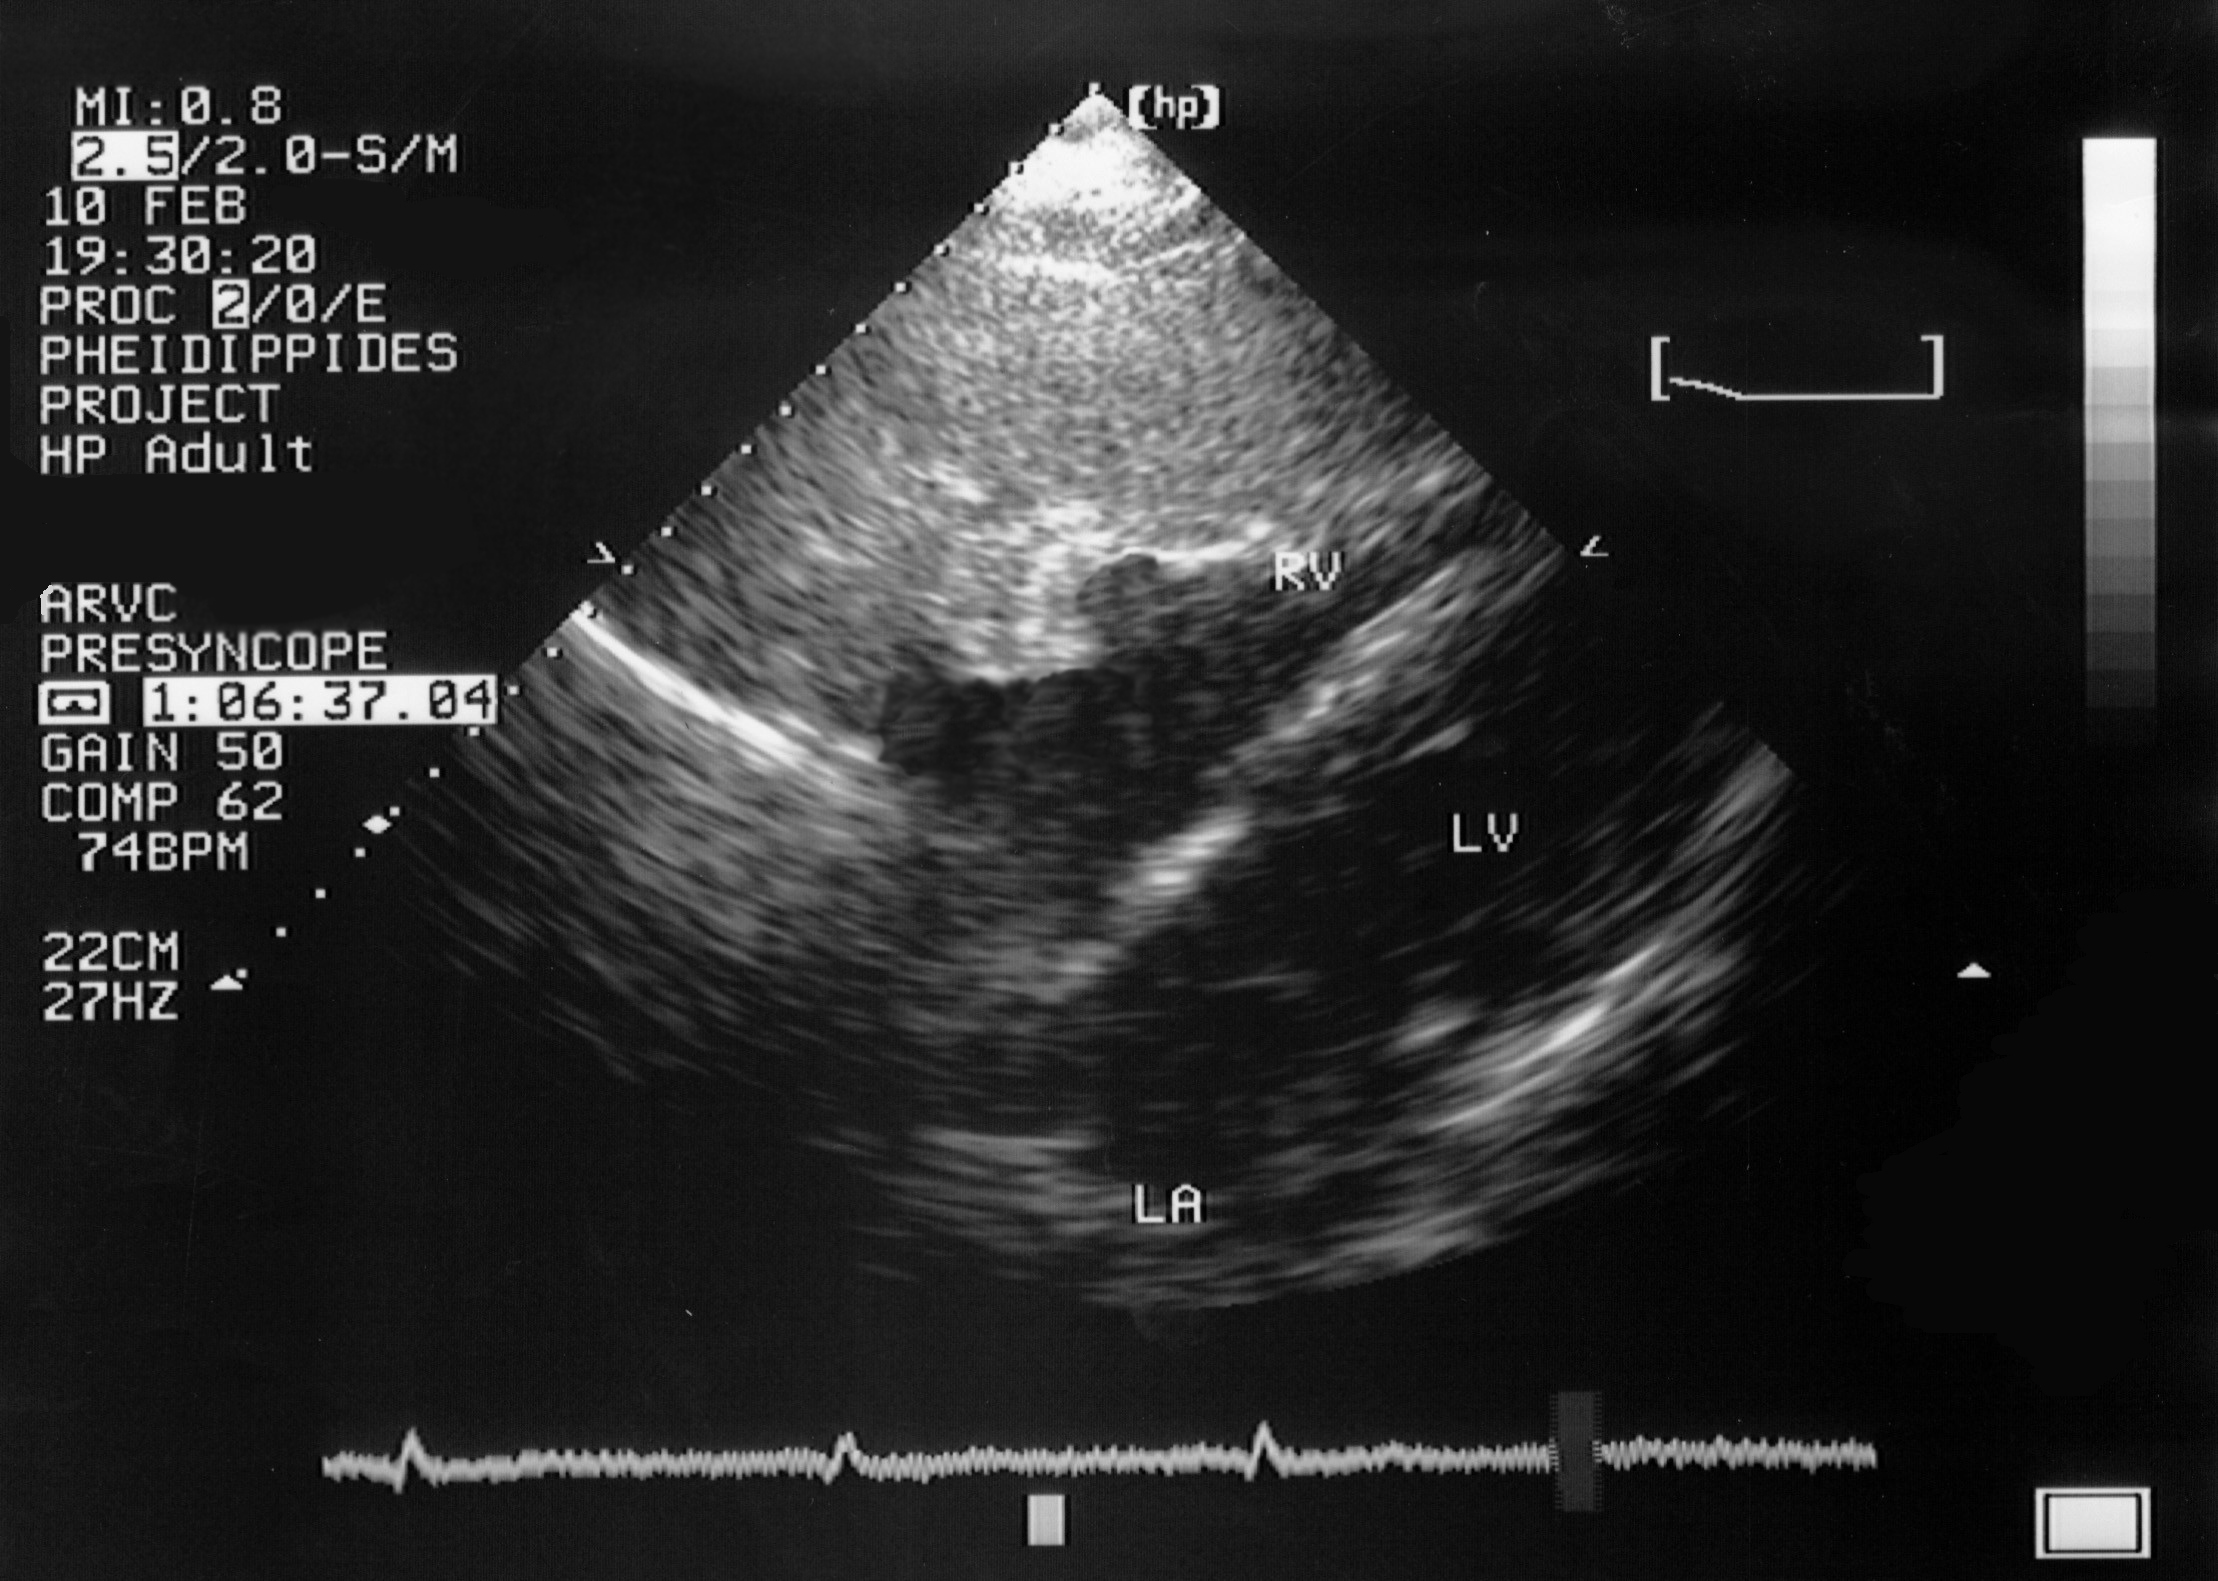

A 23-year-old female professional dancer died suddenly following physical activity. Routine postmortem examination failed to establish the cause of death. No cardiac structural abnormalities were revealed. She had a history of presyncopal episodes during the last two months preceding her sudden cardiac death (SCD). Following the proband’s death, her family was referred to our department for clinical evaluation. Following informed consent, family members were evaluated with a standard protocol. All individuals underwent detailed non-invasive evaluation followed by genetic testing.

The proband’s uncle was the first family member to undergo clinical investigation. He had been diagnosed with arrhythmogenic right ventricular cardiomyopathy/dysplasia (ARVC/D) almost 5 years before his niece’s SCD. The proband was positive for a plakophilin-2 (PKP2) mutation and both her father and uncle had a typical form of the ARVC/D disease. To strengthen our diagnostic assessment an immunohistochemical analysis was undertaken of a myocardial sample obtained at autopsy, which pointed towards ARVC. Thus, her death was attributed to ARVC. Probably, the mutation had been inherited from her paternal grandfather. Although he had never been clinically evaluated, and no tissue was available for genetic analysis, he had a history of SCD at the age of 72, thus, raising suspicions of cardiac diseaseDownloads